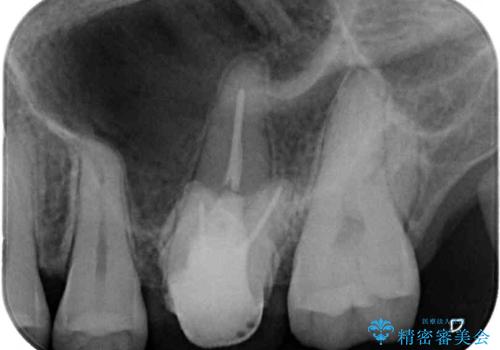

左上の銀歯は、銀歯の下に金属の土台が入っているため、その土台を除去し、ファイバーコアにやり替えて、オールセラミッククラウンにて補綴することとしました。

適合の良いセラミック治療は、むし歯再発のリスクが低いです。